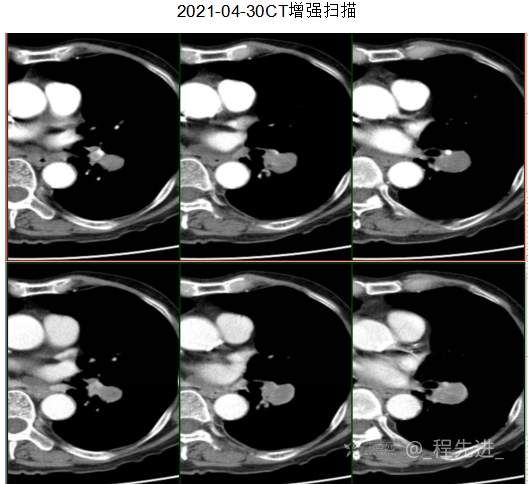

主诉: 反复咳嗽、咳痰10余年,加重10余天

现病史:患者10年前开始出现反复咳嗽、咳痰,3年前出现活动性气喘,休息后症状可缓解;冬春季节或受凉后症状加重,不伴反复下肢浮肿,曾在我院住院诊断为”慢性阻塞性肺疾病”,给予解痉平喘、化痰、输氧治疗有效,平素生活能自理,不能从事体力劳作,此次发病于10天前可能受凉后咳嗽、咳痰加重,咳黄痰,呈阵咳,咳白痰,活动气喘加重,不伴畏寒、发热,无胸痛,今来我院就诊,拟“慢性阻塞性肺病伴急性加重”收住入院,自发病以来,患者精神、食纳、睡眠一般,大小便如常,体重有下降,县体不详。患者及陪护人员:否认14天内离开过南丰,否认14天内有新型冠状病毒感染病例报告社区或中高风险地区的旅行史或居住史,否认14天内与新型冠状病毒感染的患者或无症状感染者有接触史,否认14天内曾接触过来自有病例报告社区或中高风险地区的发热或有呼吸道症状的患者,否认14天内在小范围如家庭、办公室、学校班级等场所,出现5例及以上发热和/或呼吸道症状的聚集性发病病例。